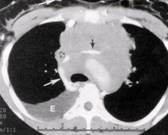

severos la utilización de circulación extracorpórea (2,4,5) (Figura 3-4).

Figura.4.

Imagen por TAC de obstrucción de vena cava y arteria

pulmonar